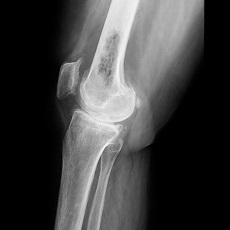

Cancer that starts in a bone is uncommon. Cancer that has spread to the bone from another part of the body is more common.

There are three types of bone cancer:

- Osteosarcoma - occurs most often between ages 10 and 19. It is more common in the knee and upper arm.

- Chondrosarcoma - starts in cartilage, usually after age 40

- Ewing's sarcoma - occurs most often in children and teens under 19. It is more common in boys than girls.

The most common symptom of bone cancer is pain. Other symptoms vary, depending on the location and size of the cancer. Surgery is often the main treatment for bone cancer. Other treatments may include amputation, chemotherapy, and radiation therapy. Because bone cancer can come back after treatment, regular follow-up visits are important.